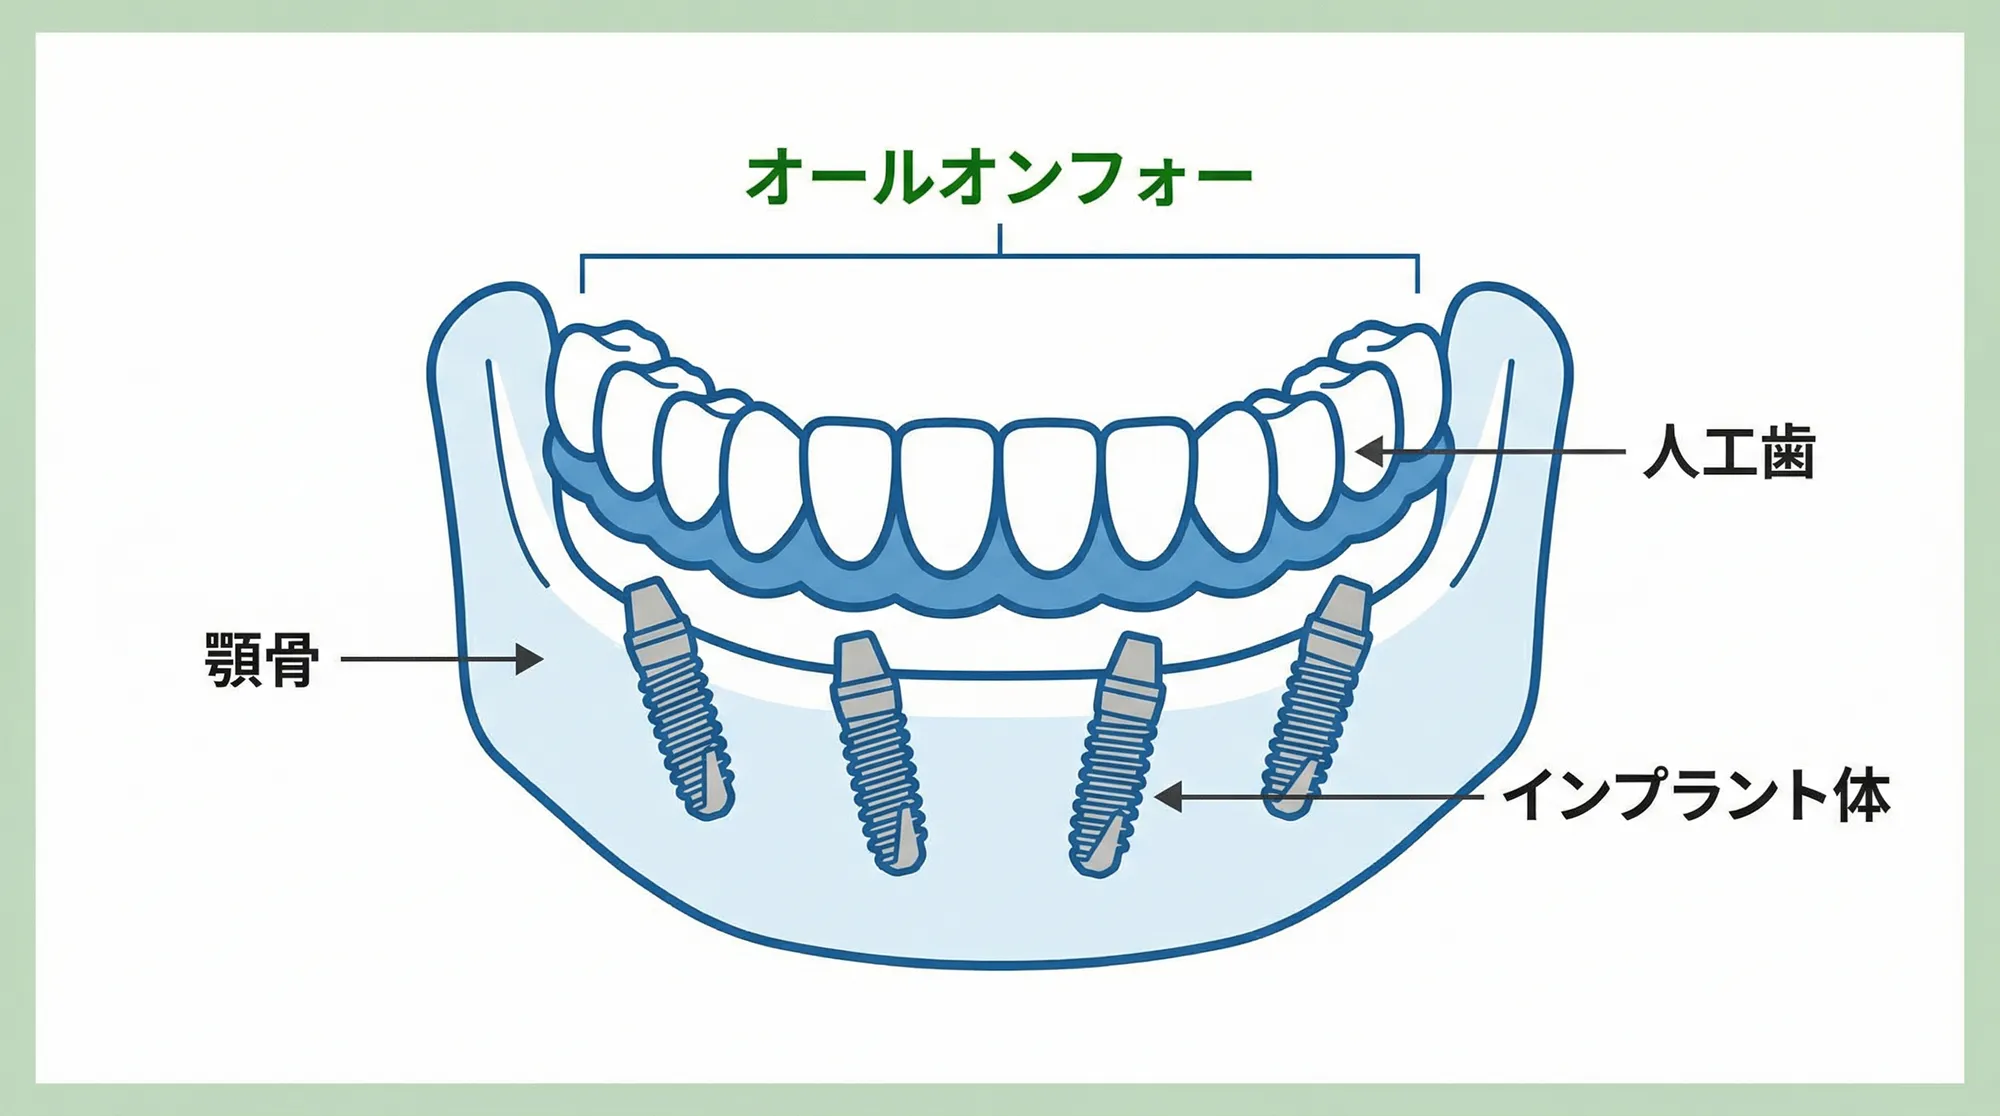

オールオン4・6とは

オールオン4・6は、4〜6本のインプラントで片顎すべての歯を支える効果的な治療法です。

従来のインプラント治療では、失った歯の本数分だけインプラントを埋入する必要がありました。しかしオールオン4・6なら、通常8〜10本必要なインプラントが4〜6本で済むため、身体的にも経済的にも負担を大幅に軽減できます。

インプラントを4〜6本埋入し、それを支えに12本の固定性の歯を装着する方法です。取り外しは必要ありません。歯ぐきでは負担しない構造のため、一般的に入れ歯と比べて痛みが出にくいとされています。